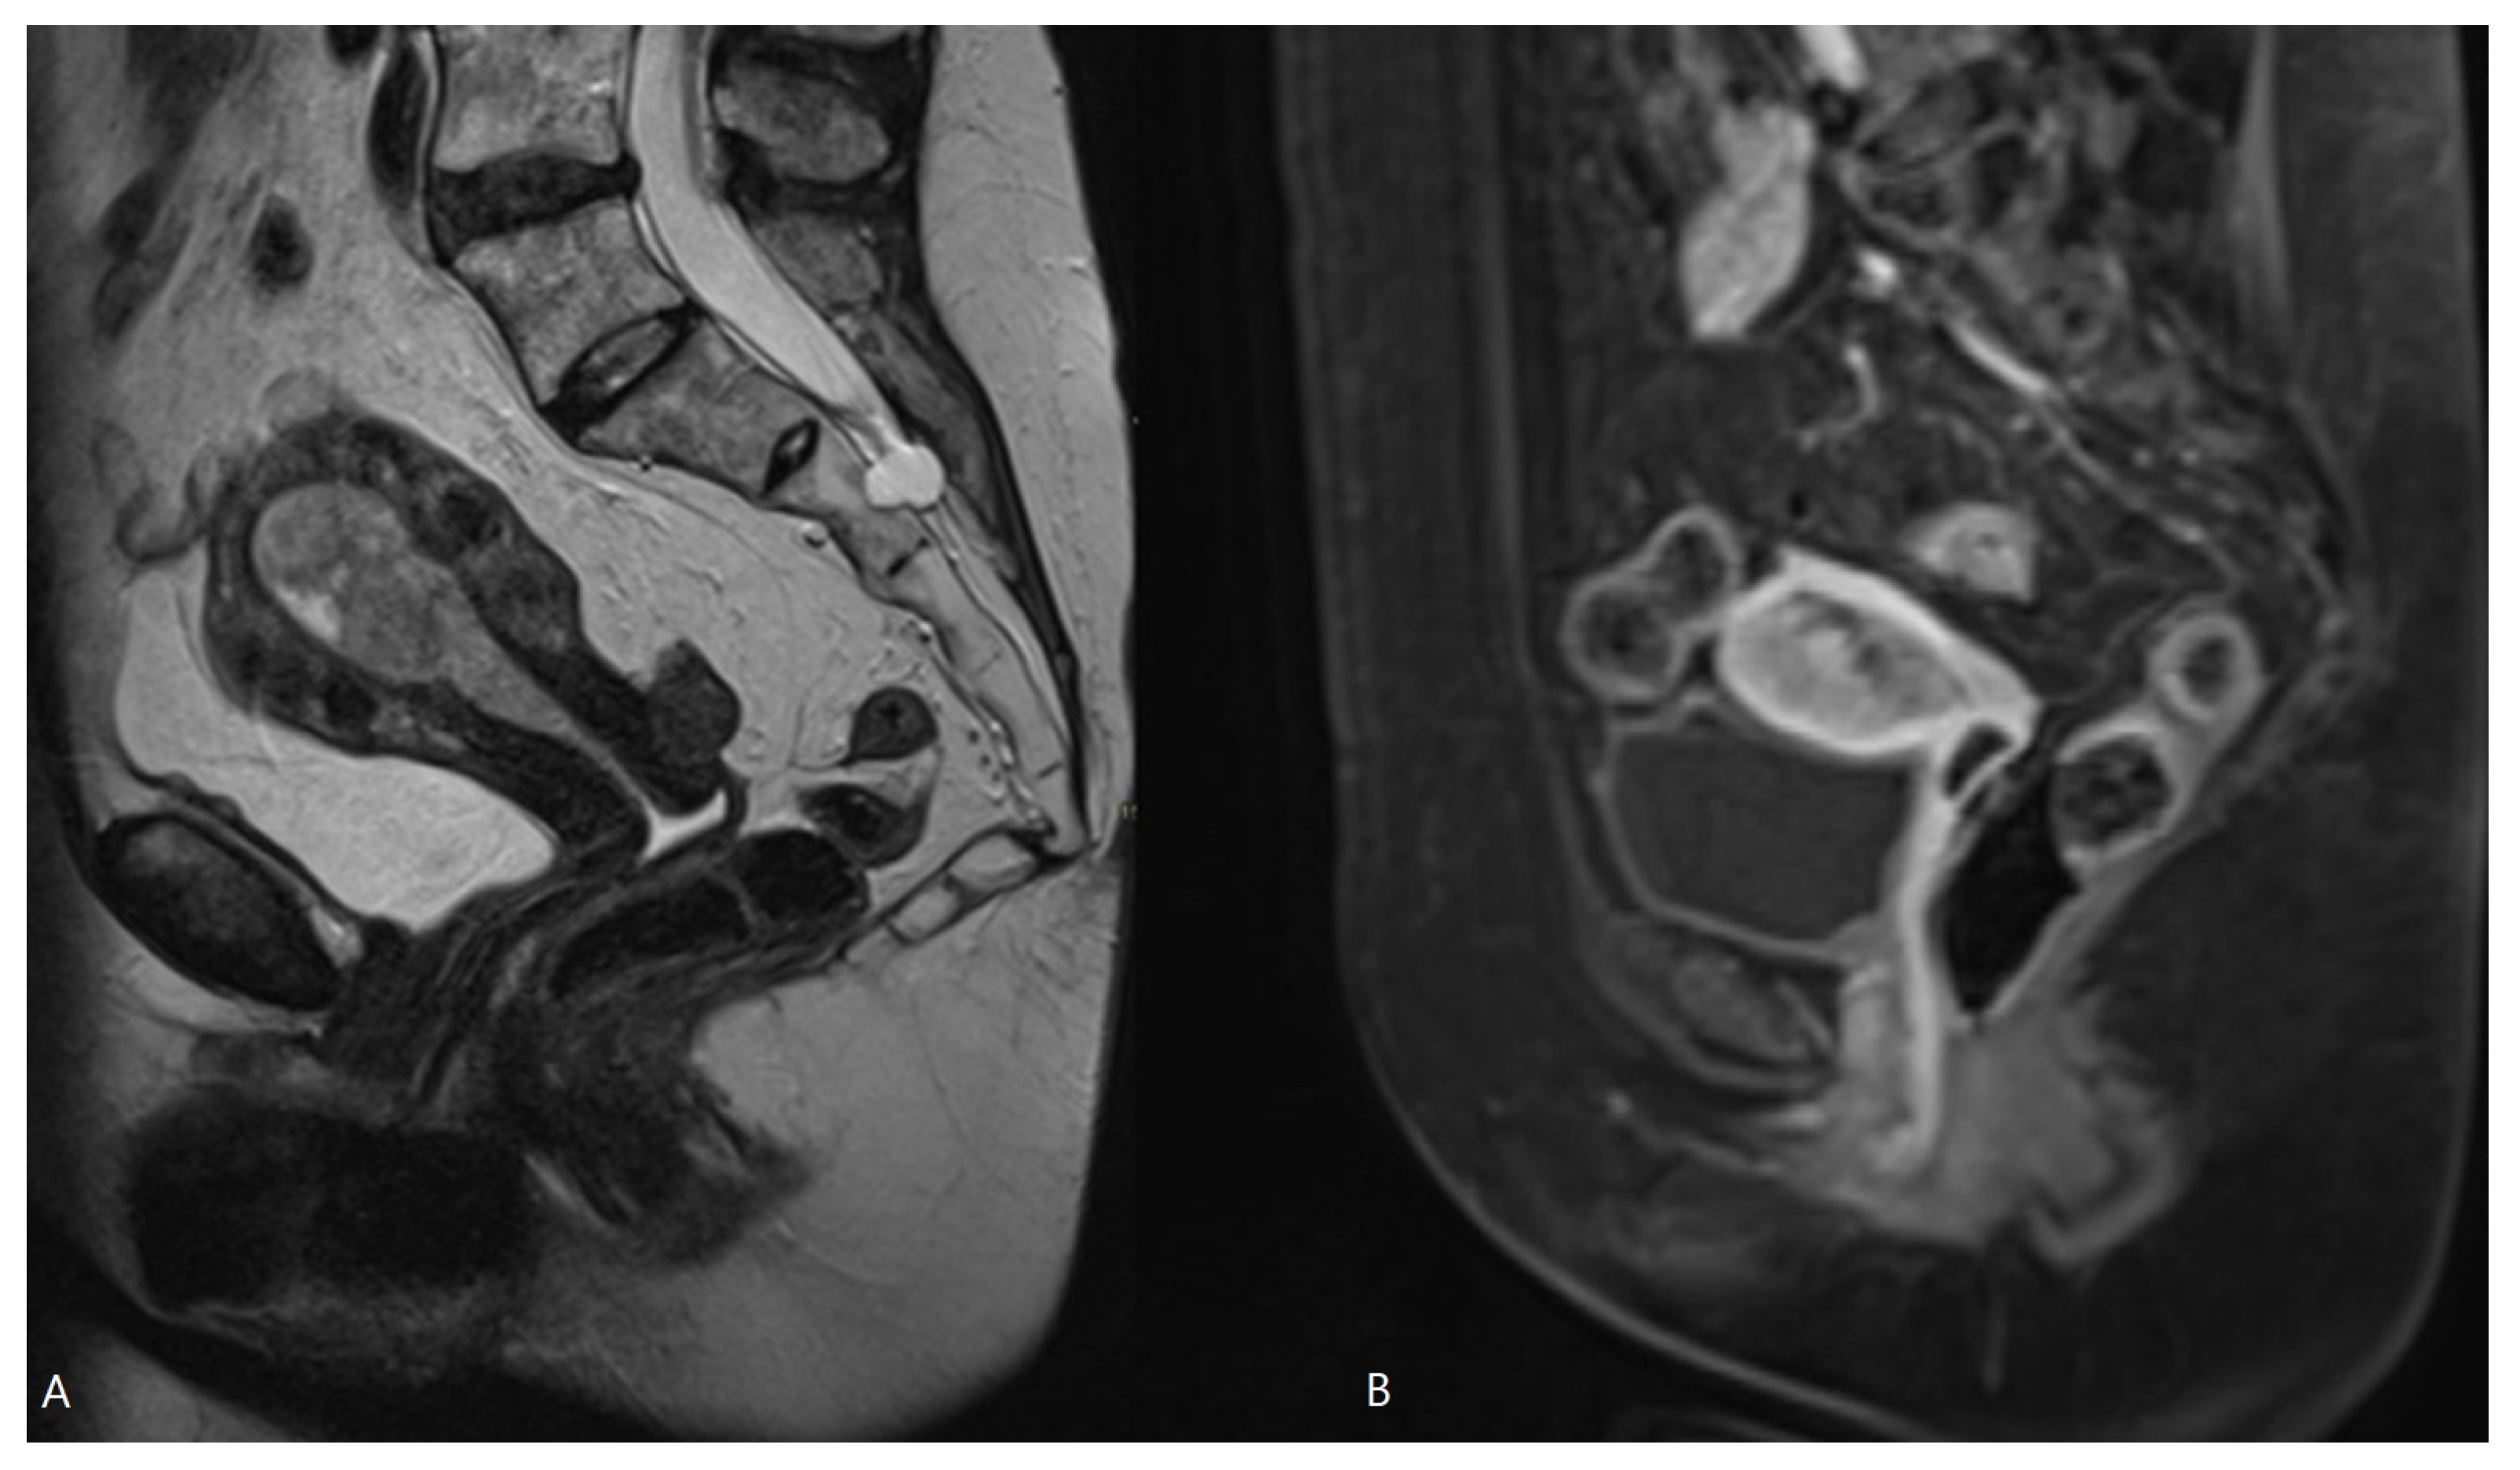

Figure 4.

MRI of EC with bulging in the endocervical canal. Sagittal T2-WI (A) and sagittal T1-WI after Gadolinium administration (B). Histopathologically, this was pT1b disease, but in MRI there is risk of overstaging because tumor extension into the endocervical canal does not account for stage T2, which is preserved for cervical stromal invasion.